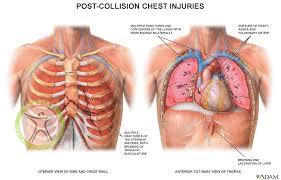

شکستگی دنده و یا ترک خوردگی آن اکثرا در اثر ضربات سنگین که به صورت مستقیم به قفسه سینه وارد می شود مانند تصادف و همچنین سقوط از ارتفاع به وجود می آید. این شکستگی میتواند در هر یک از 12 جفت دنده اتفاق بیفتد.

در صورتیکه ضربه و آسیب وارد شده به قفسه سینه شدید باشد می تواند به ارگان های داخلی نیز آسیب جدی وارد کند.

همچنین شکستگی های جدی نیز در دنده اتفاق می افتد که علائم آن عبارتند از:

در چنین شرایطی هر دو دست را در هر طرف سینه ورزشکار آسیب دیده قرار دهید و حرکت سینه را در حین تنفس بررسی کنید اگر طی دم یک طرف سینه بالا و طرف دیگر پایین برود در سمت پایین رفته سینه حداقل سه دنده شکسته وجود دارد این وضعیت قفسه سینه شناور نامیده می شود.